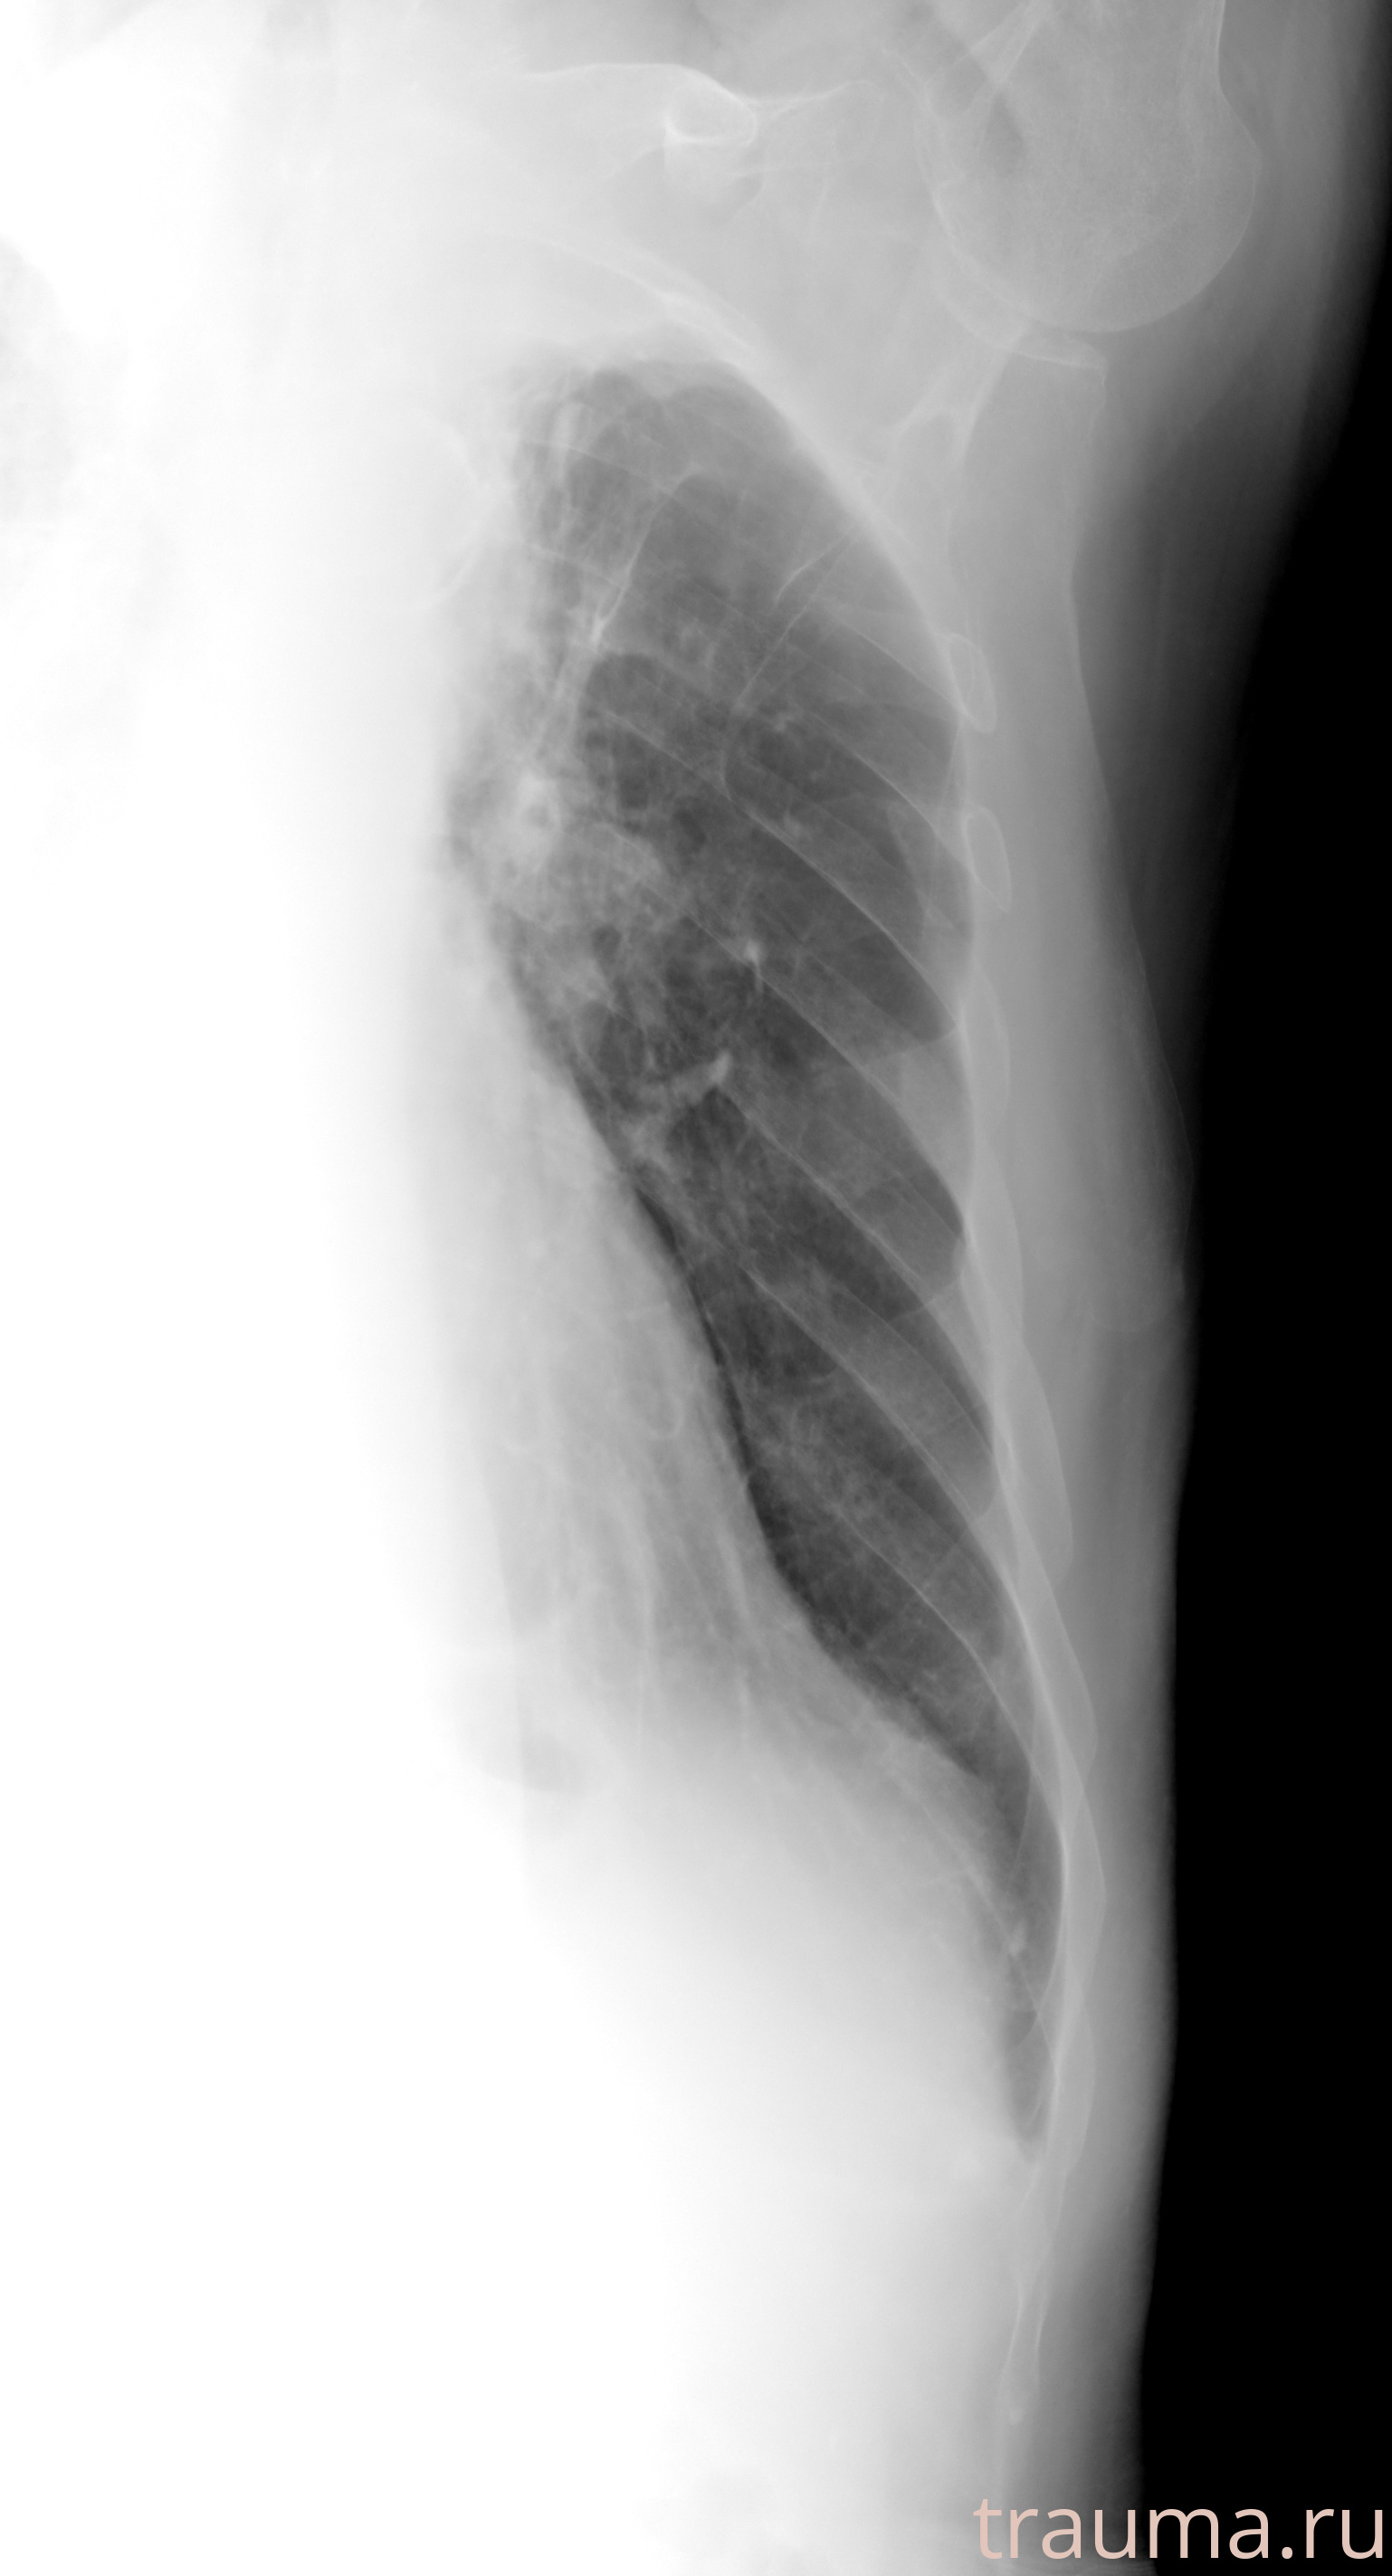

Рентгенограммы

Рентген на дому: по вашему адресу приезжает врач-рентгенолог, травматолог-ортопед с мобильным рентгеновским аппаратом, проводит диагностику травмы или заболевания, делает необходимые рентгенограммы, дает рекомендации по дальнейшему лечению. Получить качественные снимки в домашних условиях возможно благодаря уникальной методике, разработанной МосРентген Центром для института  Склифосовского

Яркость: 1   Контраст: 1   Инвертировать: 0 Увеличение: 1

Перетаскивайте мышь вверх/вниз для контраста, влево/право для яркости. Прокрутка колесом изменяет масштаб. Нажмите Сбросить для возврата к исходному изображению. При увеличении держите мышь в той области, которую хотите рассмотреть.